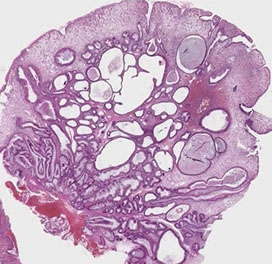

Brunner Gland polyps

Unique to duodenum and reside in submucosa

ducts communicate to lumen opening in crypts bwt intestinal villi; make an alkaline mucus that neutralizes acidic luminal contents and protects mucosa from autodigestion

- Glands usually in tightly packed aggs c grey PAS+ cytoplasm and small basally located nuclei

- Brunners glands can normally be increased in reactive lesions (commonly c Chronic Peptic Duodenitis [CPD]), where can extend into lamina propria and cause the appearance of a nodule

- best to avoid the term "Brunner gland adenoma" bc do not normally produce dysplasia or ca

Brunner gland hyperplasia / hamartoma is a pedunculated polyp c Brunner glands and surrounding fibrous stroma that is usually >2 cm

- can present c intussusception, bleeding, or obstruction and can be large and well-defined

- Micro: submucosal-based mass c intact overlyingh mucosa c nests of b9 Brunner glands separated by sm muscle and vascular septa assoc c areas of cystic change

- larger polyps can produce sx of obstruction

Small lesions can be dx'd as Brunner gland polyp bc may be a hamartoma, or neoplastic

Crushed Brunner glands can look like neural or mesenchymal lesions; and a PAS highlights the bright pink Brunner glands